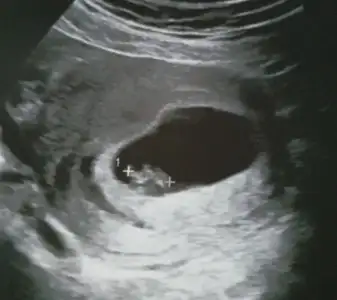

Kizlar Havalianne__ Havalianne__ bana da yorum yaparmisiniz ilki 6+4 haftalik

2cide ise 10+6 görüntüde altta da yaziyor. Her ikiside karindan bu arada